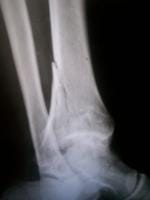

Su opinión fractura

Agradeceria su opinion en esta fractura ya llevo 1.7 meses con yeso 49 años varón que pronostico puede hacer